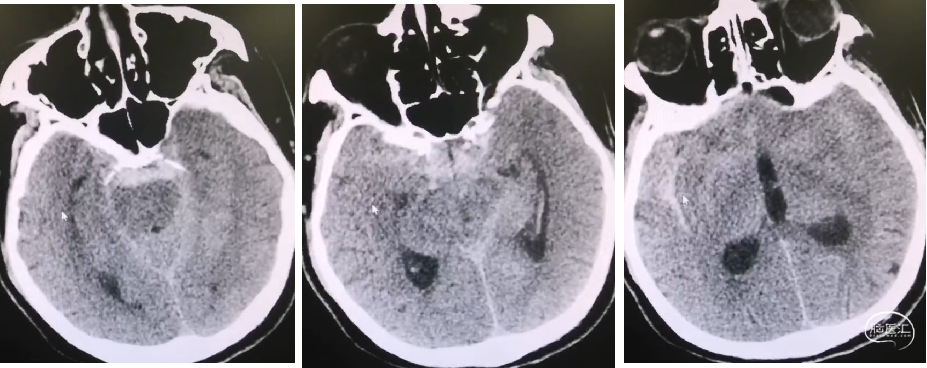

入院CT

术后第一天CT